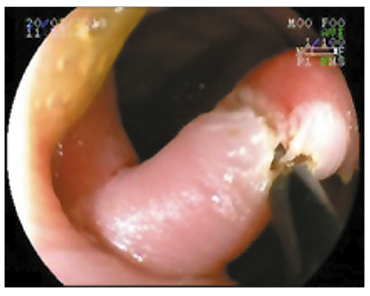

Se discutió con equipo de coloproctología las opciones respecto del abordaje terapéutico, considerando que no existía un beneficio significativo del proctológico sobre el endoscópico, y se optó en conjunto por la vía endoscópica. Se seccionó el puente mucoso con papilotomo de punta (Needle Knife, Boston, Scientifics, Natick, Massachusetts), se utilizó corriente de corte-coagulación con unidad electroquirúrgica ERBE ICC 200 (Efecto 3, 120-60 W), sin incidentes (Figuras 3 y 4).

Se consideró la opción de realizar ligaduras laterales previas a la sección del puente mucoso, pero debido a que estos mismos son característicamente muy poco vascularizados, con baja probabilidad de sangrado en agudo y diferido, se optó por utilizar corte únicamente, contando con el instrumental necesario (clips) frente a la eventualidad de sangrado.